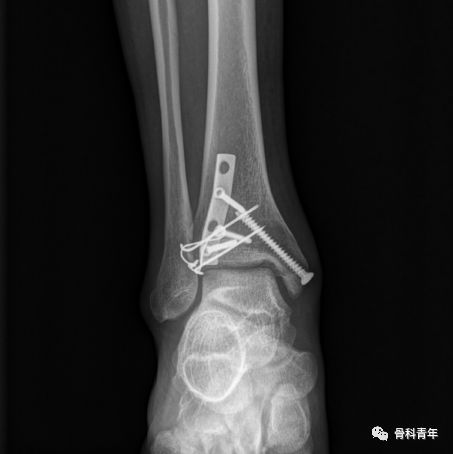

手术技巧:Chaput结节骨折的张力带固定方法!

Chaput结节骨折在旋转型踝关节骨折中较为常见,距骨外旋挤压外踝,导致下胫腓韧带损伤或下经下胫腓韧带止点的撕脱骨折,胫骨止点的撕脱为Chaput结节骨折,亦称“前踝骨折”,外踝止点的撕脱骨折即为Wagstaff结节骨折。螺钉固定时最主流的固定方法,但该方法需要骨块足够大并较为完整,否则螺钉置入后存在骨块碎裂风险;对较为粉碎的Chaput结节骨折,推荐一期小钢板内固定。

也有学者采用锚钉固定,将骨块通过锚钉缝线固定于胫骨远端,但该方法的总体固定强度不如内固定。考虑到张力带原则在腱-骨连接处骨折中的广泛应用,如髌骨、内踝等,有研究人员开始采用克氏针张力带技术固定Chaput骨块:

步骤1:前外侧切口暴露Chaput结节,小复位钳临时复位,根据Chaput骨块的大小,平行穿入两枚1.2-1.6mm克氏针,固定至胫骨远端。

步骤2:距骨折线3cm的胫骨远端,置入一枚4mm松质骨螺钉,绕螺钉即克氏针尾部,0.8mm钢丝“8”字固定。

该固定方法并非对所有Chaput骨折均适用,需要骨块较为完整;在固定过程中,前外侧切口暴露Chaput骨块较为清楚,间隔3cm置入松质骨螺钉可能较为困难,显露不够,必要时可能需要另外切口,增加手术创伤。对骨块较小且完整,螺钉固定易致骨块碎裂者,此方法可能较为适用。